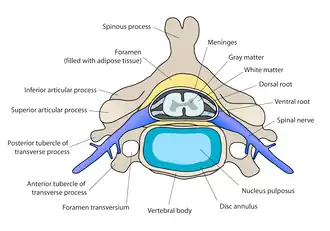

Intervertebral discs consist of an outer fibrous ring, the anulus (or annulus) fibrosus disci intervertebralis, which surrounds an inner gel-like center, the nucleus pulposus.[1]

The anulus fibrosus consists of several layers (laminae) of fibrocartilage made up of both type I and type II collagen. Type I is concentrated toward the edge of the ring, where it provides greater strength. The stiff laminae can withstand compressive forces.

The fibrous intervertebral disc contains the nucleus pulposus and this helps to distribute pressure evenly across the disc. This prevents the development of stress concentrations which could cause damage to the underlying vertebrae or to their endplates. The nucleus pulposus contains loose fibers suspended in a mucoprotein gel. The nucleus of the disc acts as a shock absorber, absorbing the impact of the body's activities and keeping the two vertebrae separated. It is the remnant of the notochord.[2]

Anulus fibrosus

Anulus fibrosus -